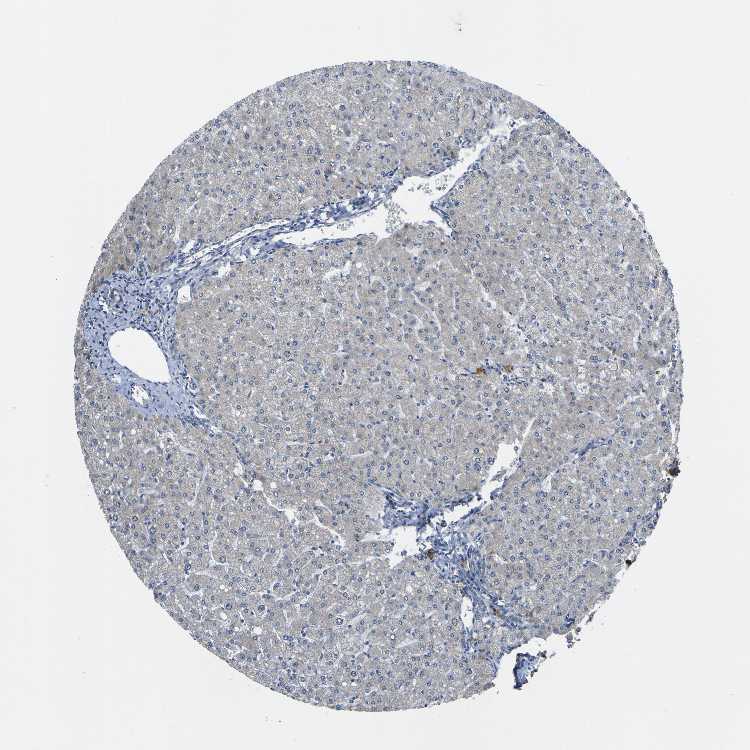

Tissue expression of LDLR Staining in liver The Human Protein Atlas Protein Atlas Ldlr  Low density lipoprotein receptor (hgnc symbol) entrez gene summary: Correlation analysis based on mrna. The pathology section contains mrna and protein expression data from 17 different forms of human cancer. The structure section provides predicted structures from the alphafold protein structure database and includes. If you continue, we'll assume that you. Protein structure for human protein ldlr (ldlcq2) we use. Protein Atlas Ldlr.

From www.proteinatlas.org